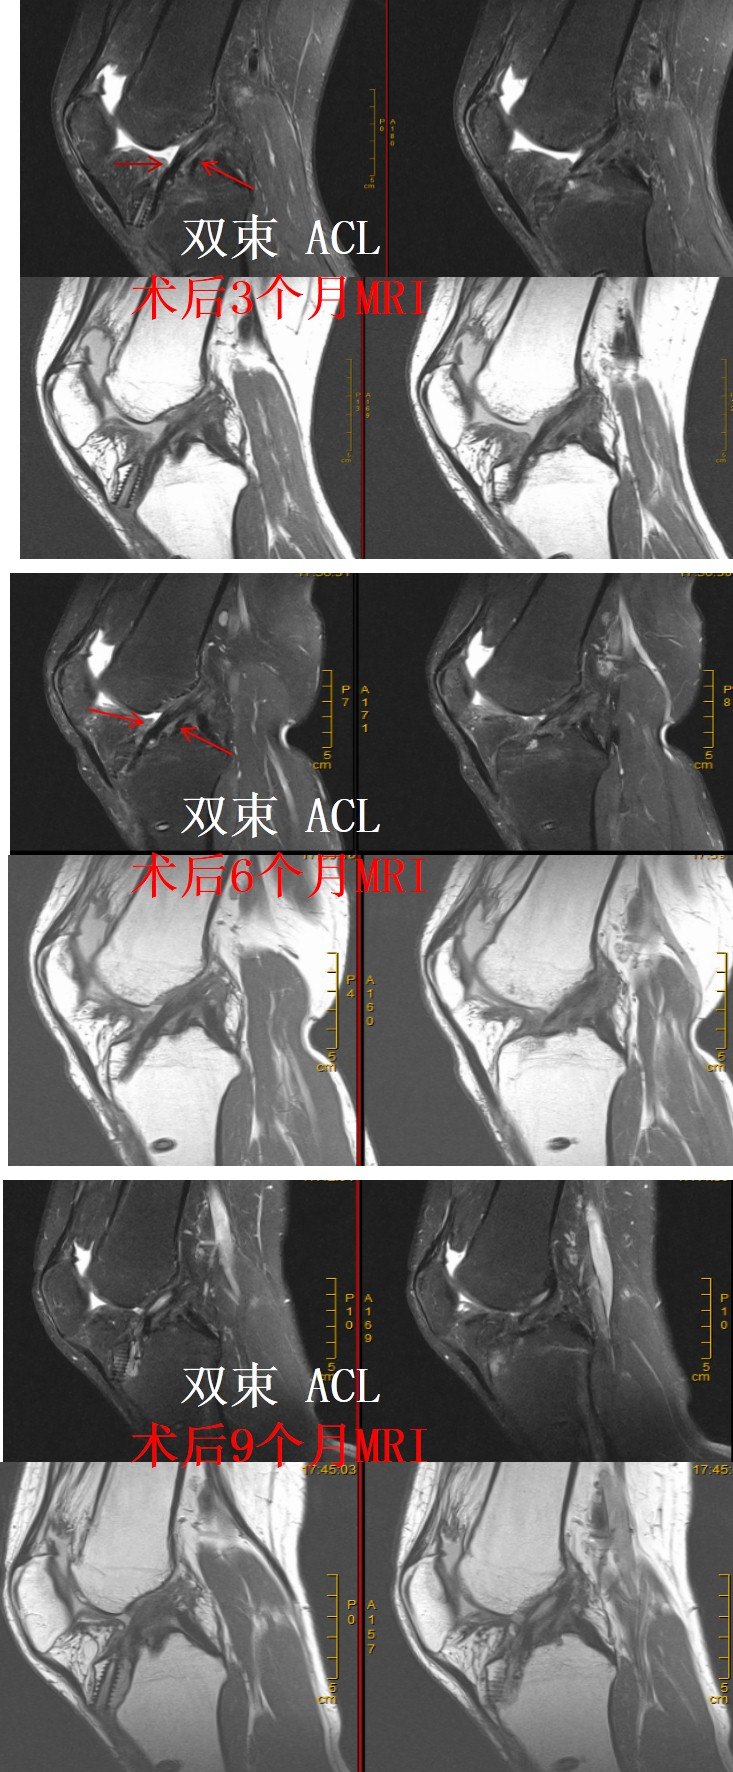

也有些患者在前交叉韧带重建术后3个月到半年,韧带已经塑形十分完好!

目前,大部分患者进行前交叉韧带重建为单束重建,也有一些患者适合双束重建,双束前交叉韧带重建后韧带的愈合与塑形过程与单束韧带的愈合和塑形过程是一样的。